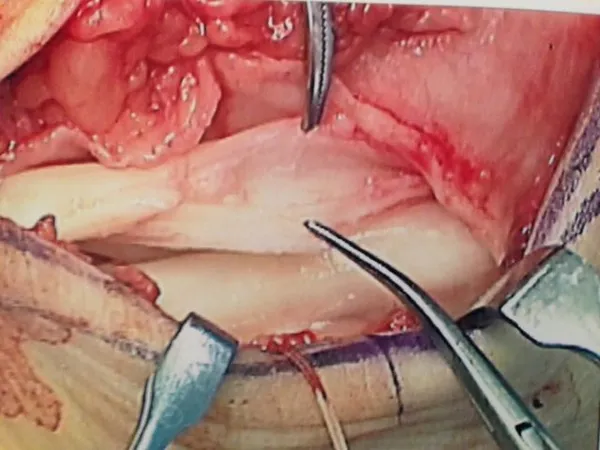

Below, dislocated peroneal tendons are being repaired and reduced to the anatomic location.

The tendons are dislocated to the outside of the fibula instead of behind.

These are intraoperative pics of a woman who traumatically dislocated her peroneal tendons in a fall.

These are pics of the peroneus longus dislocated over the fibula. The instrument on the bottom is pointing towards the tendon. The instrument on the top left is showing where the tendon should be.

This is a pic of us relocating the tendons.